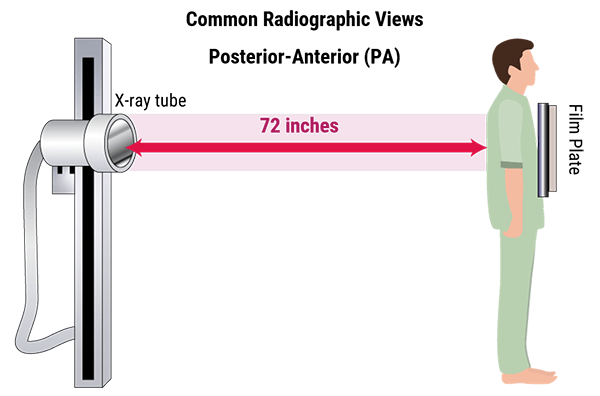

X-rays travel in straight lines in air at a distance of 72 inches from the detector. They diverge in all directions and are attenuated by the housing around the cathode ray tube and by the collimator filters. The structures that the beam hits first, will be magnified in relation to those which are nearer the detector.

Three terms are used to describe positioning: source-object distance SOD, where the object represents the patient; object-image distance OID, where the image is the detector; and source-image distance SID.

To represent an image with as little magnification as possible, the X-ray tube should be placed 72 inches from the image receptor.

X-ray images are shadows of the anatomy represented on the image receptor. The farther the object is from the image receptor, the more magnified it becomes.

The method of similar triangles is used to show the effects of moving the patient and the detector. To reduce magnification the X-ray source can be moved further away from the patient. Organs that need to be measured accurately, should be placed closer to the detector.

Chest x-ray is one of the most common imaging tests performed in clinical practice, typically for cough, chest pain, and shortness of breath, chest wall trauma, and assessment of occult disease. The two images show the difference between AP and PA images in representing the heart shadow size. Standard x-rays are performed with the patient standing facing the x-ray film or the digital cassette. The tube emits x-rays through the patient from back to front, reducing the magnification of the heart and other anterior structures that are situated close to the film in the PA position.

As a conclusion, a PA beam view of the chest allows more accurate representation of heart size as the heart is positioned closer to the detector and is therefore less magnified.

Heart is positioned closer to the detector and is therefore less magnified